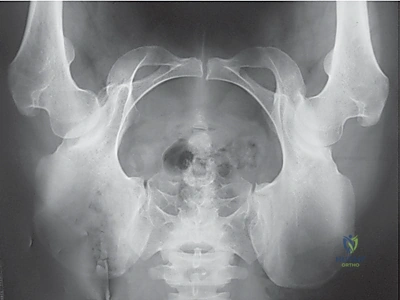

2. الأشعة السينية (X-rays): بأوضاع محددة لقياس زوايا التغطية (مثل زاوية CE وزاوية Tönnis) وتحديد درجة خلل التنسج.

بعد تحرير التجويف، يقوم الدكتور هطيف بتدويره في ثلاثة أبعاد (3D) ليغطي رأس عظمة الفخذ بشكل مثالي. يتم التحقق من التغطية الجديدة باستخدام جهاز الأشعة السينية الفلوروسكوبي داخل غرفة العمليات لضمان الزوايا المثالية.